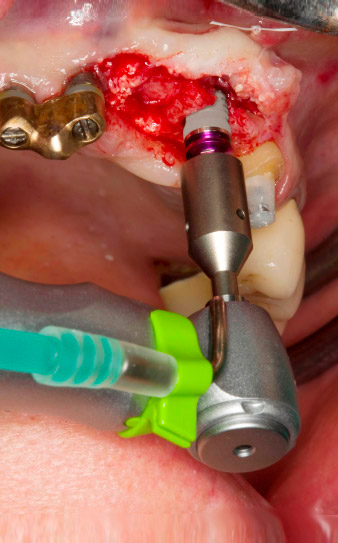

Gewindeschnitt mit dem Winkelstück WS-75 L

Abb. 3: Gewindeschnitt mit dem Winkelstück WS-75 L bei einer Übersetzung von 20:1 (Programm P4). Hilfreich sind hier das hohe Drehmoment des Implantmed, das Hexagon-Spannsystem für sichere Kraftübertragung und die automatische Umkehr der Drehrichtung bei zu hohem Widerstand.

Maschinelles Eindrehen des Implantats

Abb. 4: Maschinelles Eindrehen des Implantats mit dem Winkelstück WS-75 L bei einer Übersetzung von 20:1 (Programm P5).